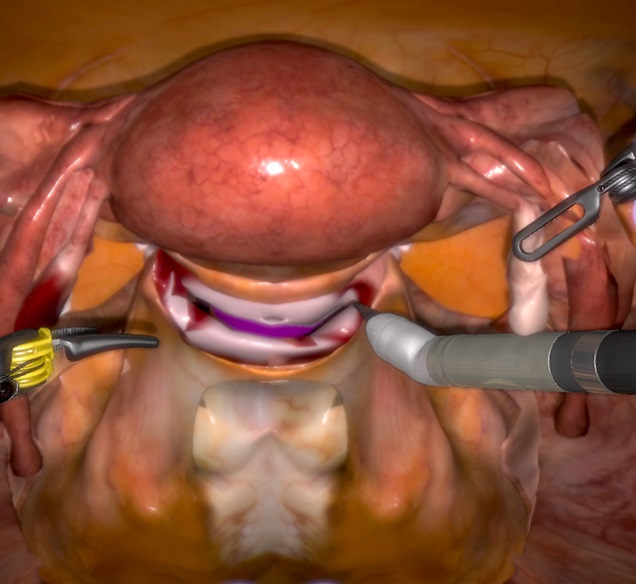

La chirurgie robotique est en train de modifier considérablement le paysage chirurgical. Ses bénéfices en termes de courbe d’apprentissage sont un de ses avantages majeurs comparativement à la coelioscopie. Cependant, l’introduction du robot au sein des blocs opératoires amène une modification des pratiques et nécessite d’autres apprentissages : l’installation, la maîtrise de la machine, la gestion des risques. Le bon déroulement de l’intervention repose sur l’ensemble de l’équipe et ce, d’autant plus que le chirurgien s’est éloigné physiquement du patient. Enfin, ce nouvel outil nous conduit à repenser l’enseignement même de la chirurgie. La simulation occupera probablement dans le futur une part importante de la formation sur le modèle de l’aéronautique. Le compagnonnage, s’il est toujours nécessaire, ne peut suffire à répondre aux exigences de cette nouvelle technologie.

De la coelioscopie à la robotique : l’optimisation de la gestuelle

La vision est en 3 dimensions avec contrôle de la caméra par le

chirurgien, les tremblements sont filtrés, les instruments

micro-articulés (rotation de 360°, 7° de liberté), le pouce et

l’index commandent les deux mors des instruments ; ainsi la

gestuelle se rapproche de celle de la laparotomie, elle est

intuitive : cela permet d’améliorer l’accessibilité, la précision

et la dextérité de l’opérateur. Enfin, le confort de celui-ci assis